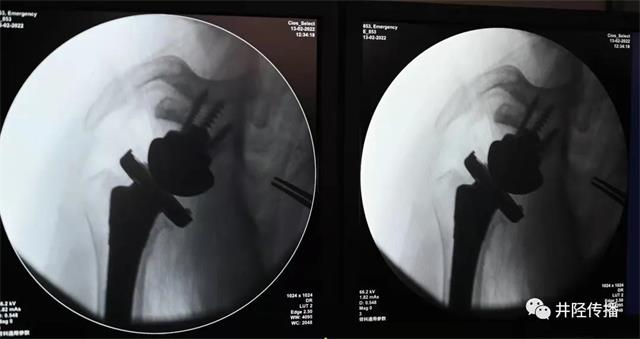

术后影像

李计东书记、李博副书记带领关节外科团队完善一系列检查后,诊断为右侧巨大肩袖损伤(不可修复型)、右肩关节炎。在麻醉科、手术室医护人员配合下,为患者实施了反肩关节置换术,1小时后手术成功完成,使张婆婆右肩重获“新生”!

目前,反肩关节置换术在国内属于肩关节领域前沿技术,只有为数不多的医院开展。该手术的开展为肩痛患者尤其是巨大肩袖撕裂无法修复等患者的治疗提供了一种新的方法与思路,同时,也标志着井陉县医院骨科在肩关节疾病诊治方面再上新台阶。